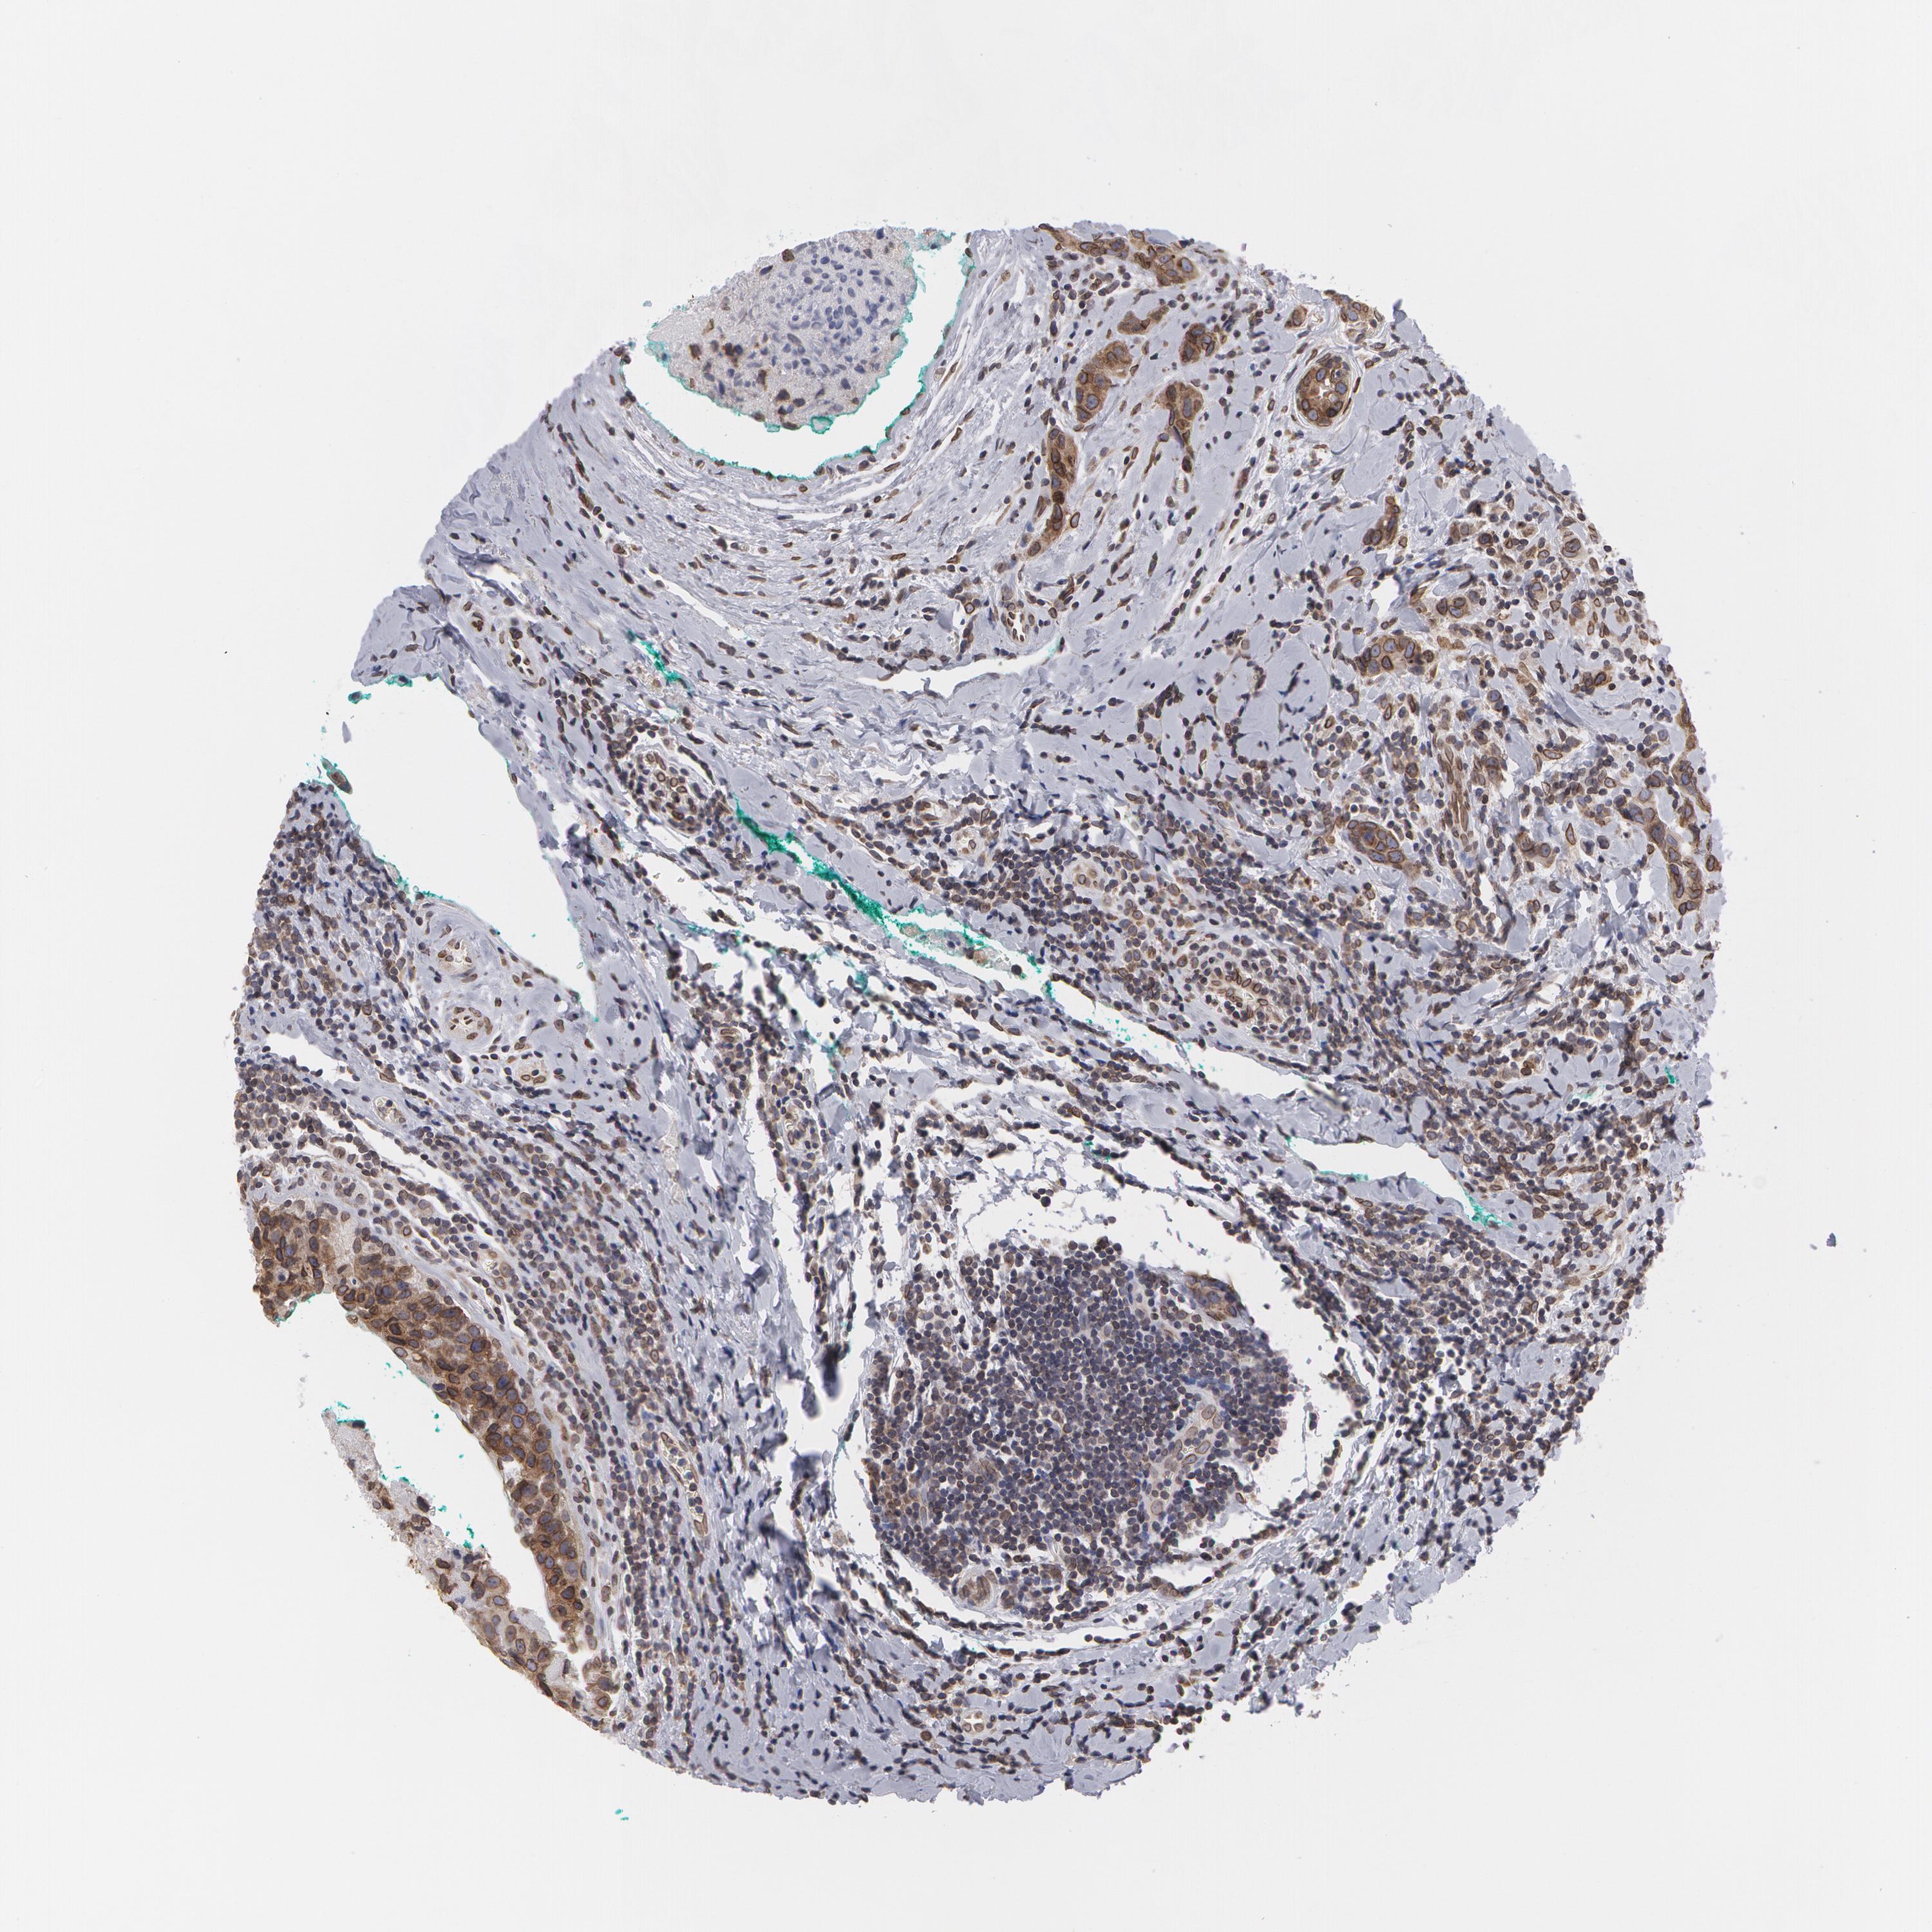

BRCA TCGA BRCA VALIDATION PROTEIN EXPRESSION